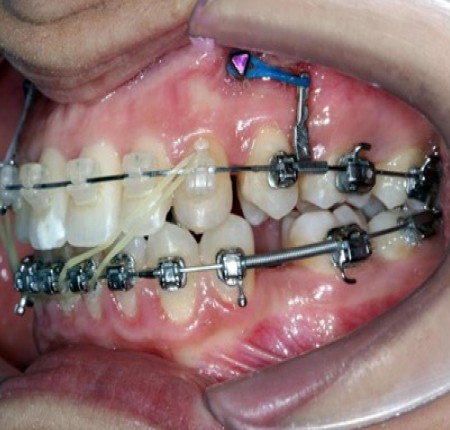

La force motrice est appliquée directement de la mini-vis à la molaire à mésialer. Sans moyen accessoire, la traction appliquée pourra être décomposée en une force mésialante et une force ingressive (Fig. 9). Son application à distance du CR entraîne une mesioversion et une rotation mésiale de la molaire, nous obligeant alors à incorporer les courbures compensatrices.

Figure 9

Figure 9 : schématisation des forces en présence sur la molaire lors d’une traction directe

Il est alors possible d’avoir recours à une potence (power arm) (Fig. 10). Cette configuration permet de rapprocher la force motrice délivrée du CR de la molaire, dans le plan sagittal, en fonction des conditions anatomiques (profondeur du vestibule, hauteur de gencive attachée)5. Plus la potence est proche du CR et plus la force délivrée aboutira à une gression pure sans mésio-version. En revanche, nous sommes toujours confrontés dans le plan occlusal à une rotation mésiale de la molaire. Cette dernière est même accentuée lors de l’utilisation d’une potence puisque ce dernier éloigne la force motrice du CR dans ce plan. Il sera alors nécessaire d’accentuer la courbure de pli de cintrage postérieur.

Figure 10 : (a) schématisation des forces en présence sur la molaire lors d’une traction directe par potence (b) Système de potence. (c) Système de potence coulissant.